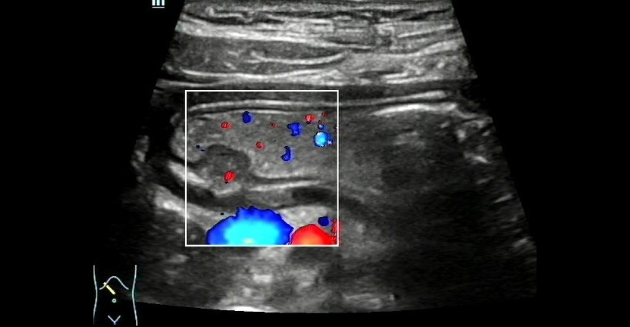

CDFI(Color Doppler Flow Imaging)? ?? ?? ??? ???? ??? mass? ??? ???? ??? ? ??? ???????. (?? 4) ??? ???? ?(stomach)? submucosal ??? ?????, ectopic pancreas? ???????.